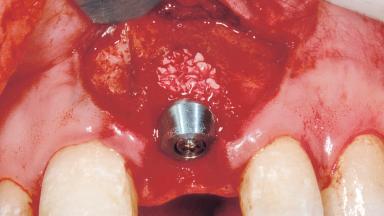

Immediate Placement of an Implant in a Maxillary Left Central Incisor Site

A 33-year-old female patient presented with an upper left central incisor that required extraction after a failed endodontic therapy. The tooth had been traumatized when the patient was a teenager and had undergone several endodontic treatments, including two apicectomy procedures. The patient was in good health and did not smoke. Clinical examination showed that the patient had a high lip line. In full smile, the gingival margins of the upper teeth were visible to the first molars. The gingival margins of central incisors 11 and 21 were only just showing. Examination of tooth 21 confirmed that the tooth was mobile and had hypererupted by 1 mm.

| Placement Protocol | Immediate implant placement |

| Tooth Site | Maxillary incisor or canine |

| Socket Morphology | Single-root socket |

| Socket Integrity | Damage to one or more bone walls |